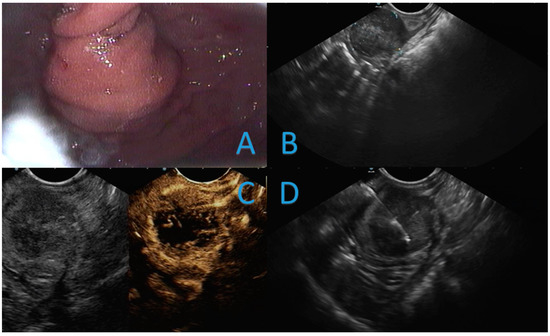

3.1. Case Report